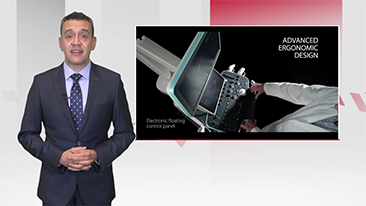

As solu??es de imagem geral Mindray Resona ajudam mĂŠdicos a obter resultados mais precisos e eficientes de diagnĂłstico e tratamento por meio de sondas de aplica??o de subdivis?es abrangentes e ferramentas eficientes de aplica??o clĂnica.